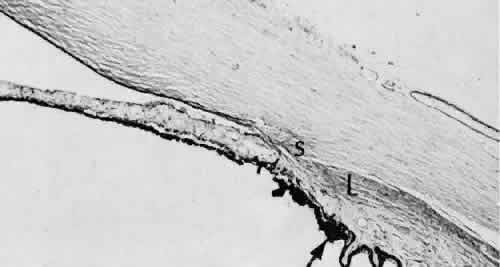

Cyclodialysis (Fig. 21) creates a cleft between the sclera and the longitudinal muscle of the ciliary body. Aqueous passes directly from the anterior chamber into the suprachoroidal space. Histologically, the longitudinal muscle of the ciliary body is disinserted from the scleral spur. Diaphanous tissue often is present in the suprachoroidal space along the route of filtration. The presence of this tissue differentiates the surgical site from artifactual disinsertion of the ciliary body, which is a common artifact of ocular tissue preparation.

Fig. 21. Light micrograph of cyclodialysis. The region of the surgical cleft between the longitudinal muscle of the ciliary body and the sclera (arrow) is filled with delicate fibrous tissue. Note the posterior location of the anterior face of the ciliary body and the angle recesses in relationship to the scleral spur (S).